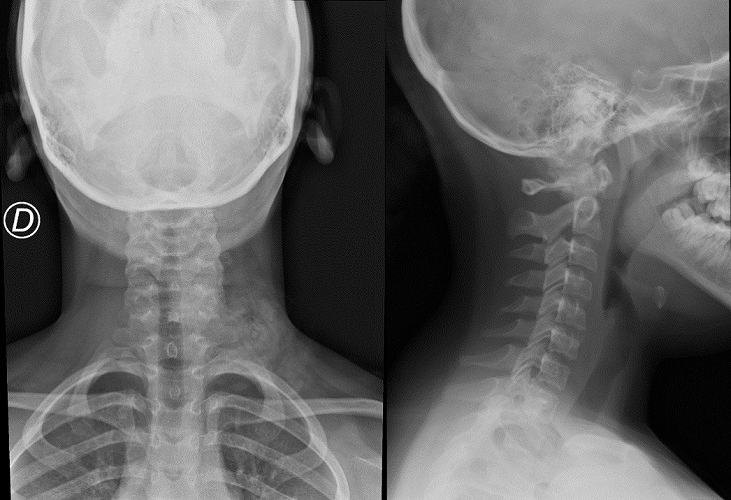

Se solicita radiografía cervical, con hallazgo de aumento de atenuación de partes blandas a nivel laterocervical izquierdo en la proyección anteroposterior (Fig. 1), que no se ve en la proyección lateral, presentando por lo demás una correcta alineación de la columna cervical sin líneas de fractura. Se consulta con el servicio de Radiología, que informa de que se trata de posible imagen artefactual debido a que el cabello está colocado sobre ese hombro. Se repite al día siguiente la radiografía con el pelo recogido, desapareciendo dicha imagen (Fig. 2).

Figura 1. Radiografía cervical anteroposterior y lateral iniciales